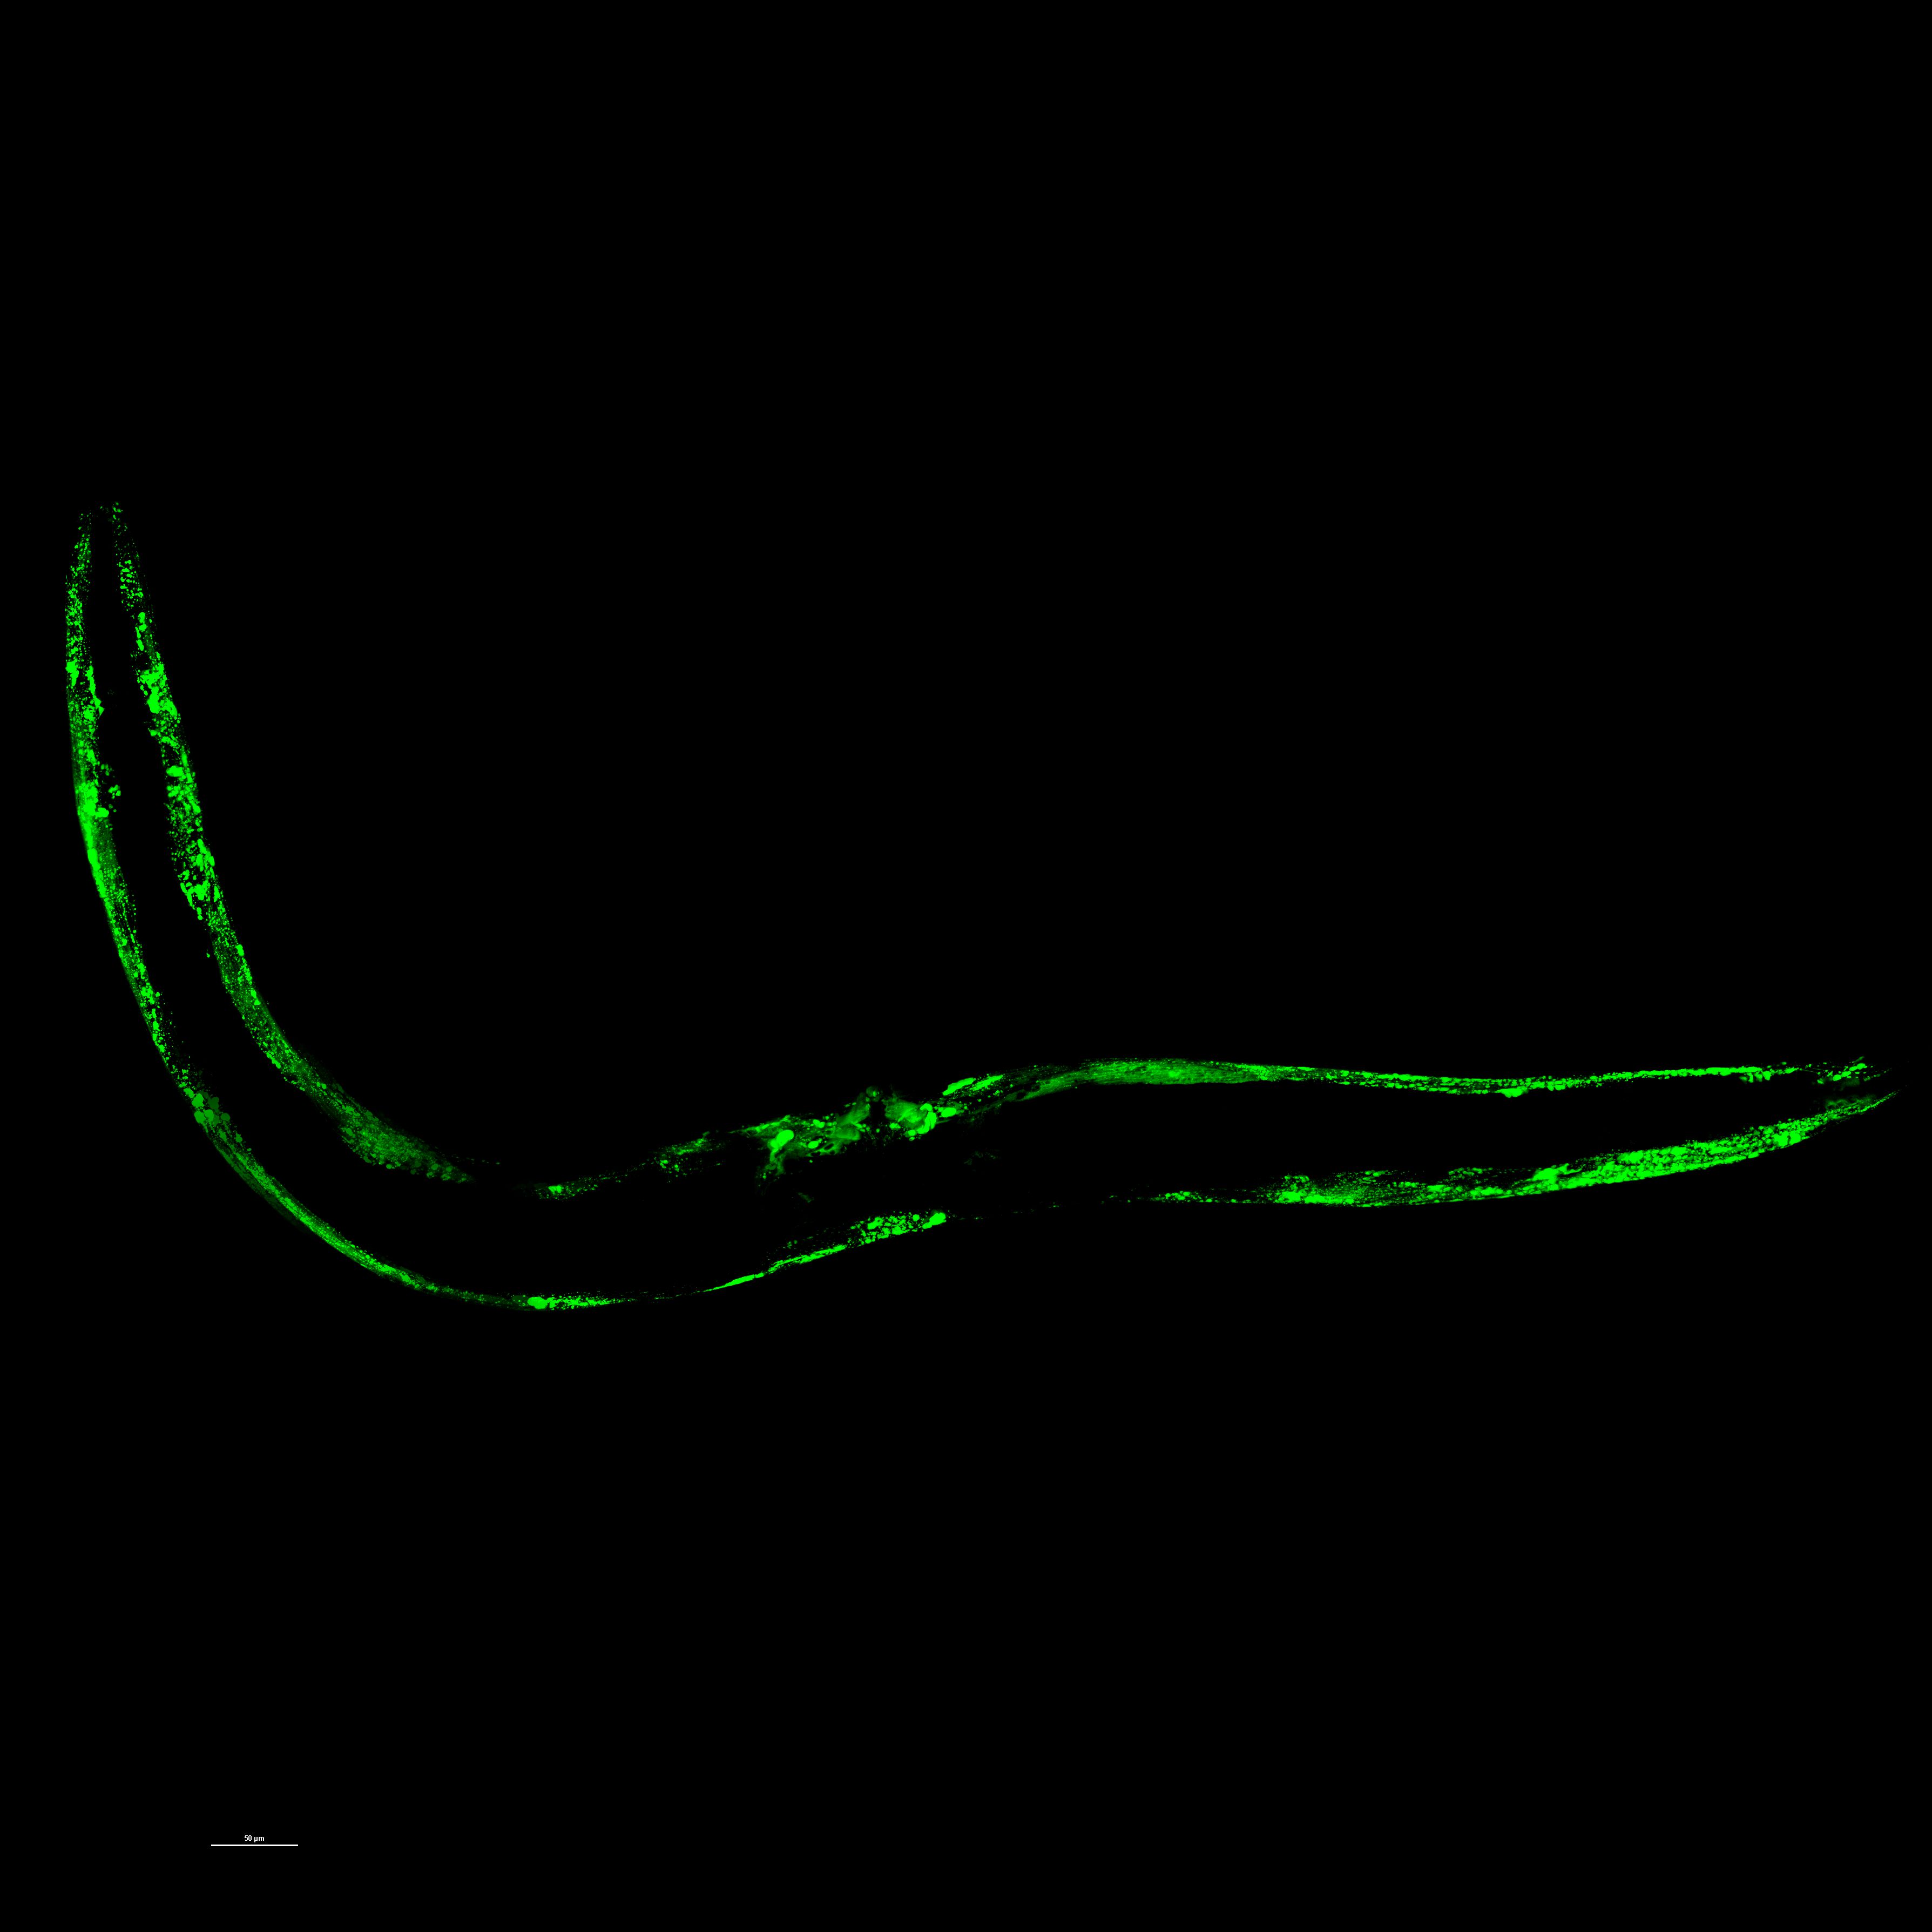

As part of the Koski Family University Fellowship, I conducted research on neurodegeneration using the nematode worm C. elegans as a model to study α-synuclein aggregation, which is associated with Parkinson’s disease. Over the course of the summer, I developed an imaging and analysis workflow involving confocal microscopy, fluorescence imaging, and quantitative assessment using ImageJ and RStudio. I tested the effect of a mannitol-based treatment on α-synuclein aggregation by imaging worms at multiple time points (days 1, 7 and 14 of adulthood) and quantifying aggregate size, count, and fluorescence intensity relative to worm size. Mannitol is a sugar alcohol compound that has shown potential as a therapeutic agent due to its ability to inhibit protein aggregation and transiently open the blood-brain barrier. I also helped refine protocols for nematode growth plate preparation and live worm imaging, gaining experience in both wet lab techniques and data processing. This project deepened my interest in translational neuroscience and taught me how to design, troubleshoot, and analyze an independent experiment from start to finish.